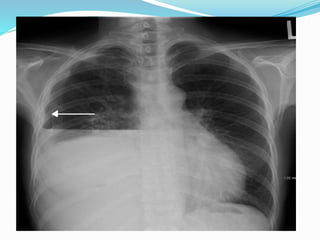

Pleural effusion with complete

right lower lobe collapse

This is a chest x ray taken from a 48y male

Who presented with left sided chest pain

Dry cough and wt loss since 4 month.

Chest x ray showed a left opaque

Thorax with mediastinal shift opposite to

Opacified side,

These findings was suggestive of a massive

Pleural effusion on clinico-radiological

Assessment.

However thoracocentesis revealed dry tap

On ultrasound of the chest disclosed a

solid, smooth marginated mass

occupying the left hemithorax with

multiple well-defined

rounded cystic spaces and focal areas of

calcification. There was no pleural effusion.